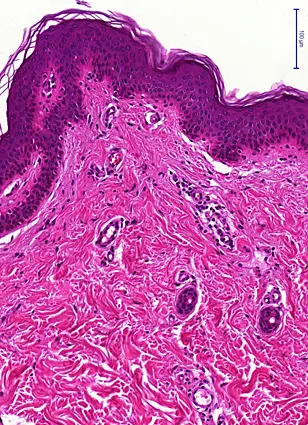

Histologisches Bild der Haut (